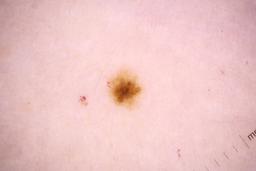

Evaluation set from the ML challenge: SIIM-ISIC Melanoma Classification.